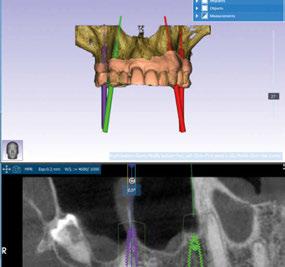

-Protocolo de planificación digital del caso mediante RealGUIDE® (STL+DICOM) (Figura 4) (Cuadro 1).

Figura 4. Planificación digital mediante RealGUIDE.

A continuación, para la planificación de los implantes dentales y el diseño de la férula de cirugía guiada se usó la plataforma digital RealGUIDE®. Para ello se realizó el matching, por un lado, del archivo STL del encerado digital; y, por otro, del archivo 3D. De esta manera, se pudo analizar el tejido óseo residual apical a cada diente y la posición de la raíz respecto a las corticales vestibular y palatina. También se estudió la relación de los contornos óseos con los tejidos blandos y con la posición final de los márgenes cervicales de la restauración protésica, pudiendo así planificar la posición 3D correcta de los implantes. En esta primera fase se diseñó una férula quirúrgica para la elevación de seno bilateral a partir del software RealGUIDE™, que nos sirvió de guía para el diseño de las ventanas de acceso. Esta férula se imprimió con la impresora 3D Formlabs® (Figura 7)

3. Fase quirúrgica final

A los 6 meses de cicatrización, se realizó un nuevo CBCT, obteniendo un nuevo archivo DICOM que alineamos con el STL del encerado. De esta manera, se planificó la posición de los implantes a 4 mm del margen de la restauración final y se diseñó y confeccionó la férula de cirugía guiada dentosoportada en 12-13 y 22-23, la cual imprimimos con la impresora 3D Formlabs®. El provisional